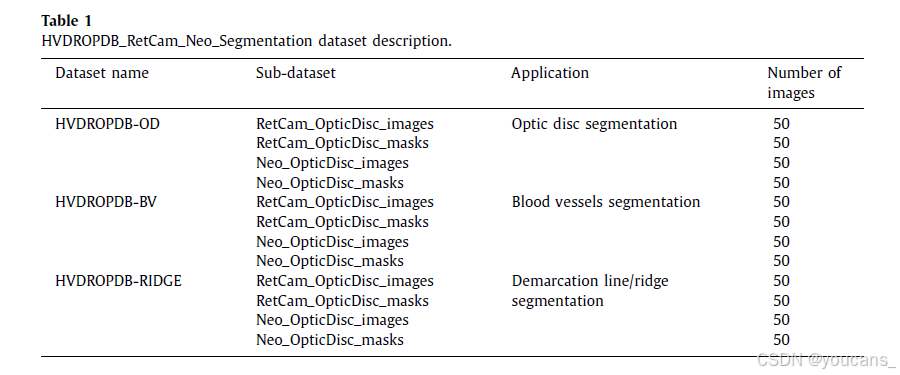

HVDROPDB_RetCam_Neo_Segmentation 数据集由 HVDROPDB-OD、HVDROPD-BV 和 HVDROPDC-RIDGE 三个主要数据集组成,分别用于视盘(Optic Disc)、血管(Blood Vessels)和分界线/脊线(Demarcation Line/Ridge)的分割。

每个主要数据集包含4个子数据集,每个子数据集包含 50幅图像及其掩模(ground truth),如表1 所示。

总共提供了 12个子数据集。

表1:HVDROPDB_RetCam_Neo_SSegmentation 数据集的描述。